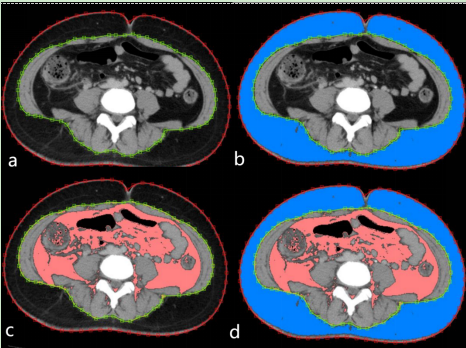

(五)胰腺炎和代謝性肝病CT/MRI檢查,針對急性胰腺炎的磁共振成像檢查能提供胰腺內(nèi)外、腹膜后間隙的病理變化圖像,為胰腺炎的嚴重程度早期評估、局部并發(fā)癥評估提供重要參考依據(jù)。肥胖癥相關(guān)的代謝性肝病磁共振成像檢查能無創(chuàng)性提供肝臟脂肪含量的情況,以及評估人體的皮下、內(nèi)臟脂肪和肌肉面積/體積相關(guān)信息,為減重手術(shù)的開展和術(shù)后影像學隨訪提供循證依據(jù)。

圖片

胰腺炎和代謝性肝病CT/MRI檢查